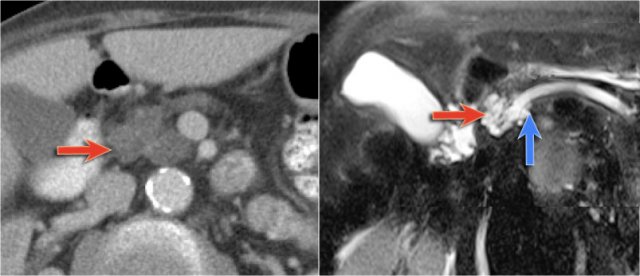

Another branch-duct IPMN found on screening with two nodules (circle and arrow).

T1W-images with fatsat before (left image) and after contrast (right image).

EUS with contrast agent revealed 2 foci without enhancement most likely mucus plugs.

6 years later the cyst was unchanged.